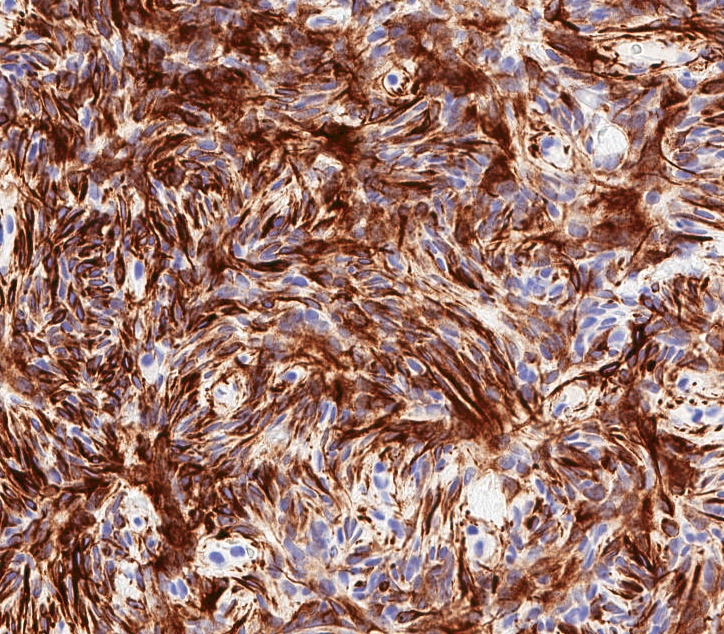

Microscopic (histologic) images

Microscopic (histologic) description

- Well circumscribed, lacks true capsule, rarely infiltrative

- Bland, uniform, short to elongated spindle cells arranged as short haphazard intersecting fascicles admixed with bands of hyalinized, brightly eosinophilic collagen and variable amounts of fat

- No more than mild nuclear atypia

- Mitoses usually absent, atypical mitoses and necrosis absent

- Mast cells common, perivascular lymphocytic infiltrates on occasion

- Focal myxoid stromal changes common

Positive stains

- Desmin (91%), vimentin, ER, PR, AR, BCL2, CD10, CD99 (Histopathology 2000;36:515, Virchows Arch 2007;450:727)

- CD34 (89%) diffuse and strong characteristic but may uncommonly show absent / focal expression (Am J Surg Pathol 2016;40:361, Breast J 2018;24:55)